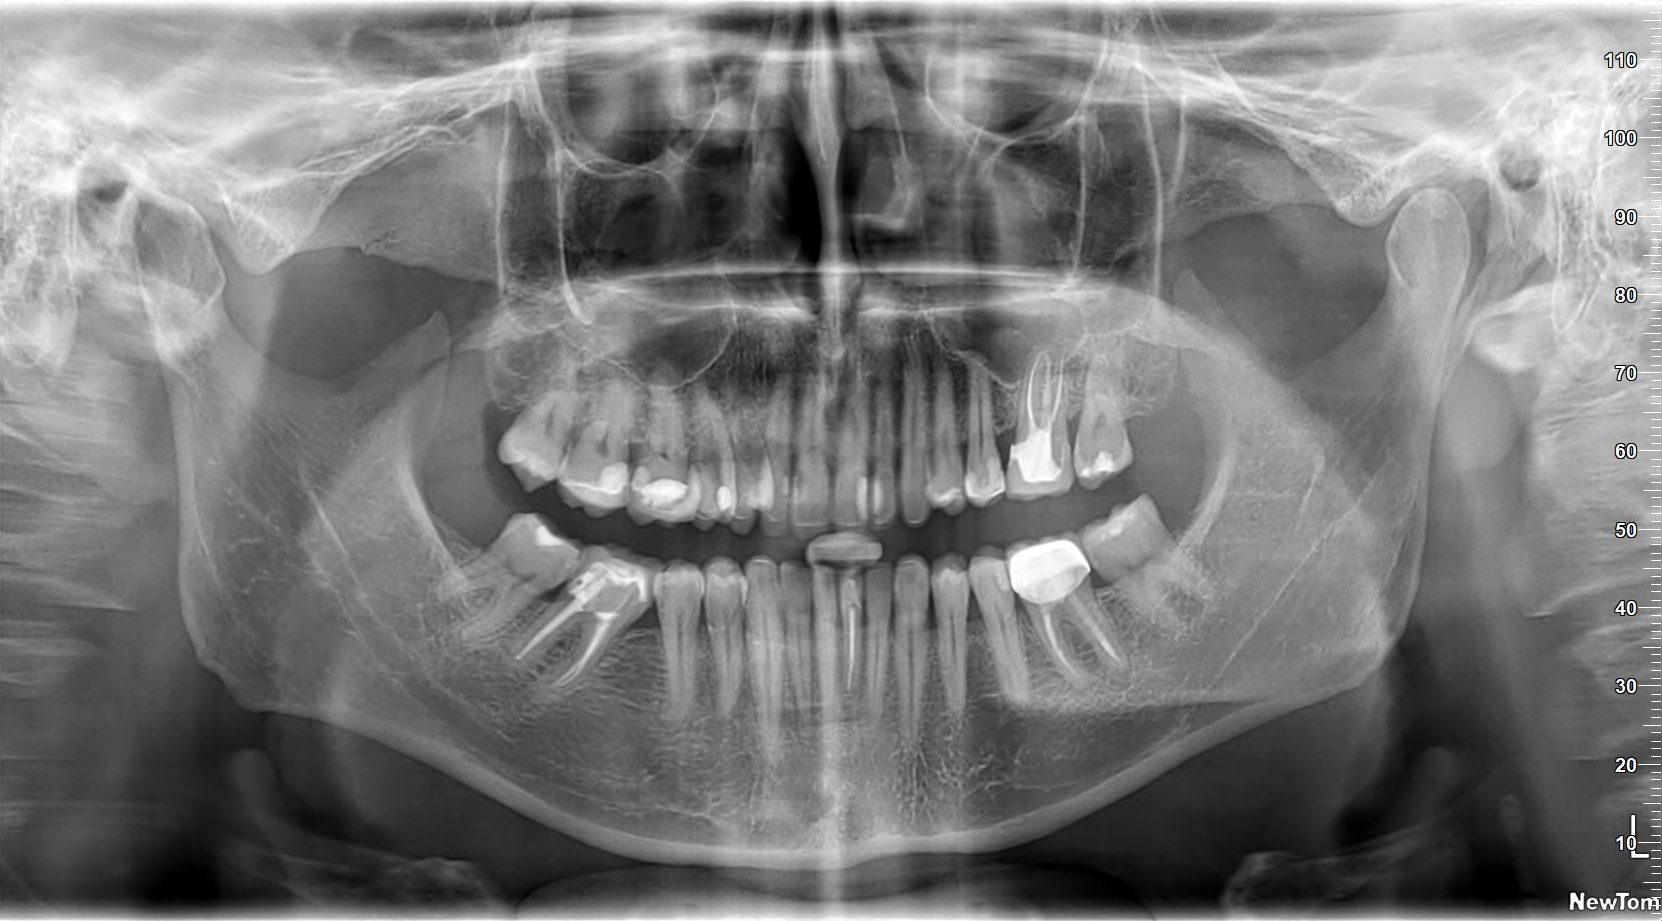

Primul pas: planul de tratament detaliat

Ai parte de un set complet de consultații. Mai mulți specialiști vor evalua multidisciplinar cazul tău. Știi de la început tot ce va urma.